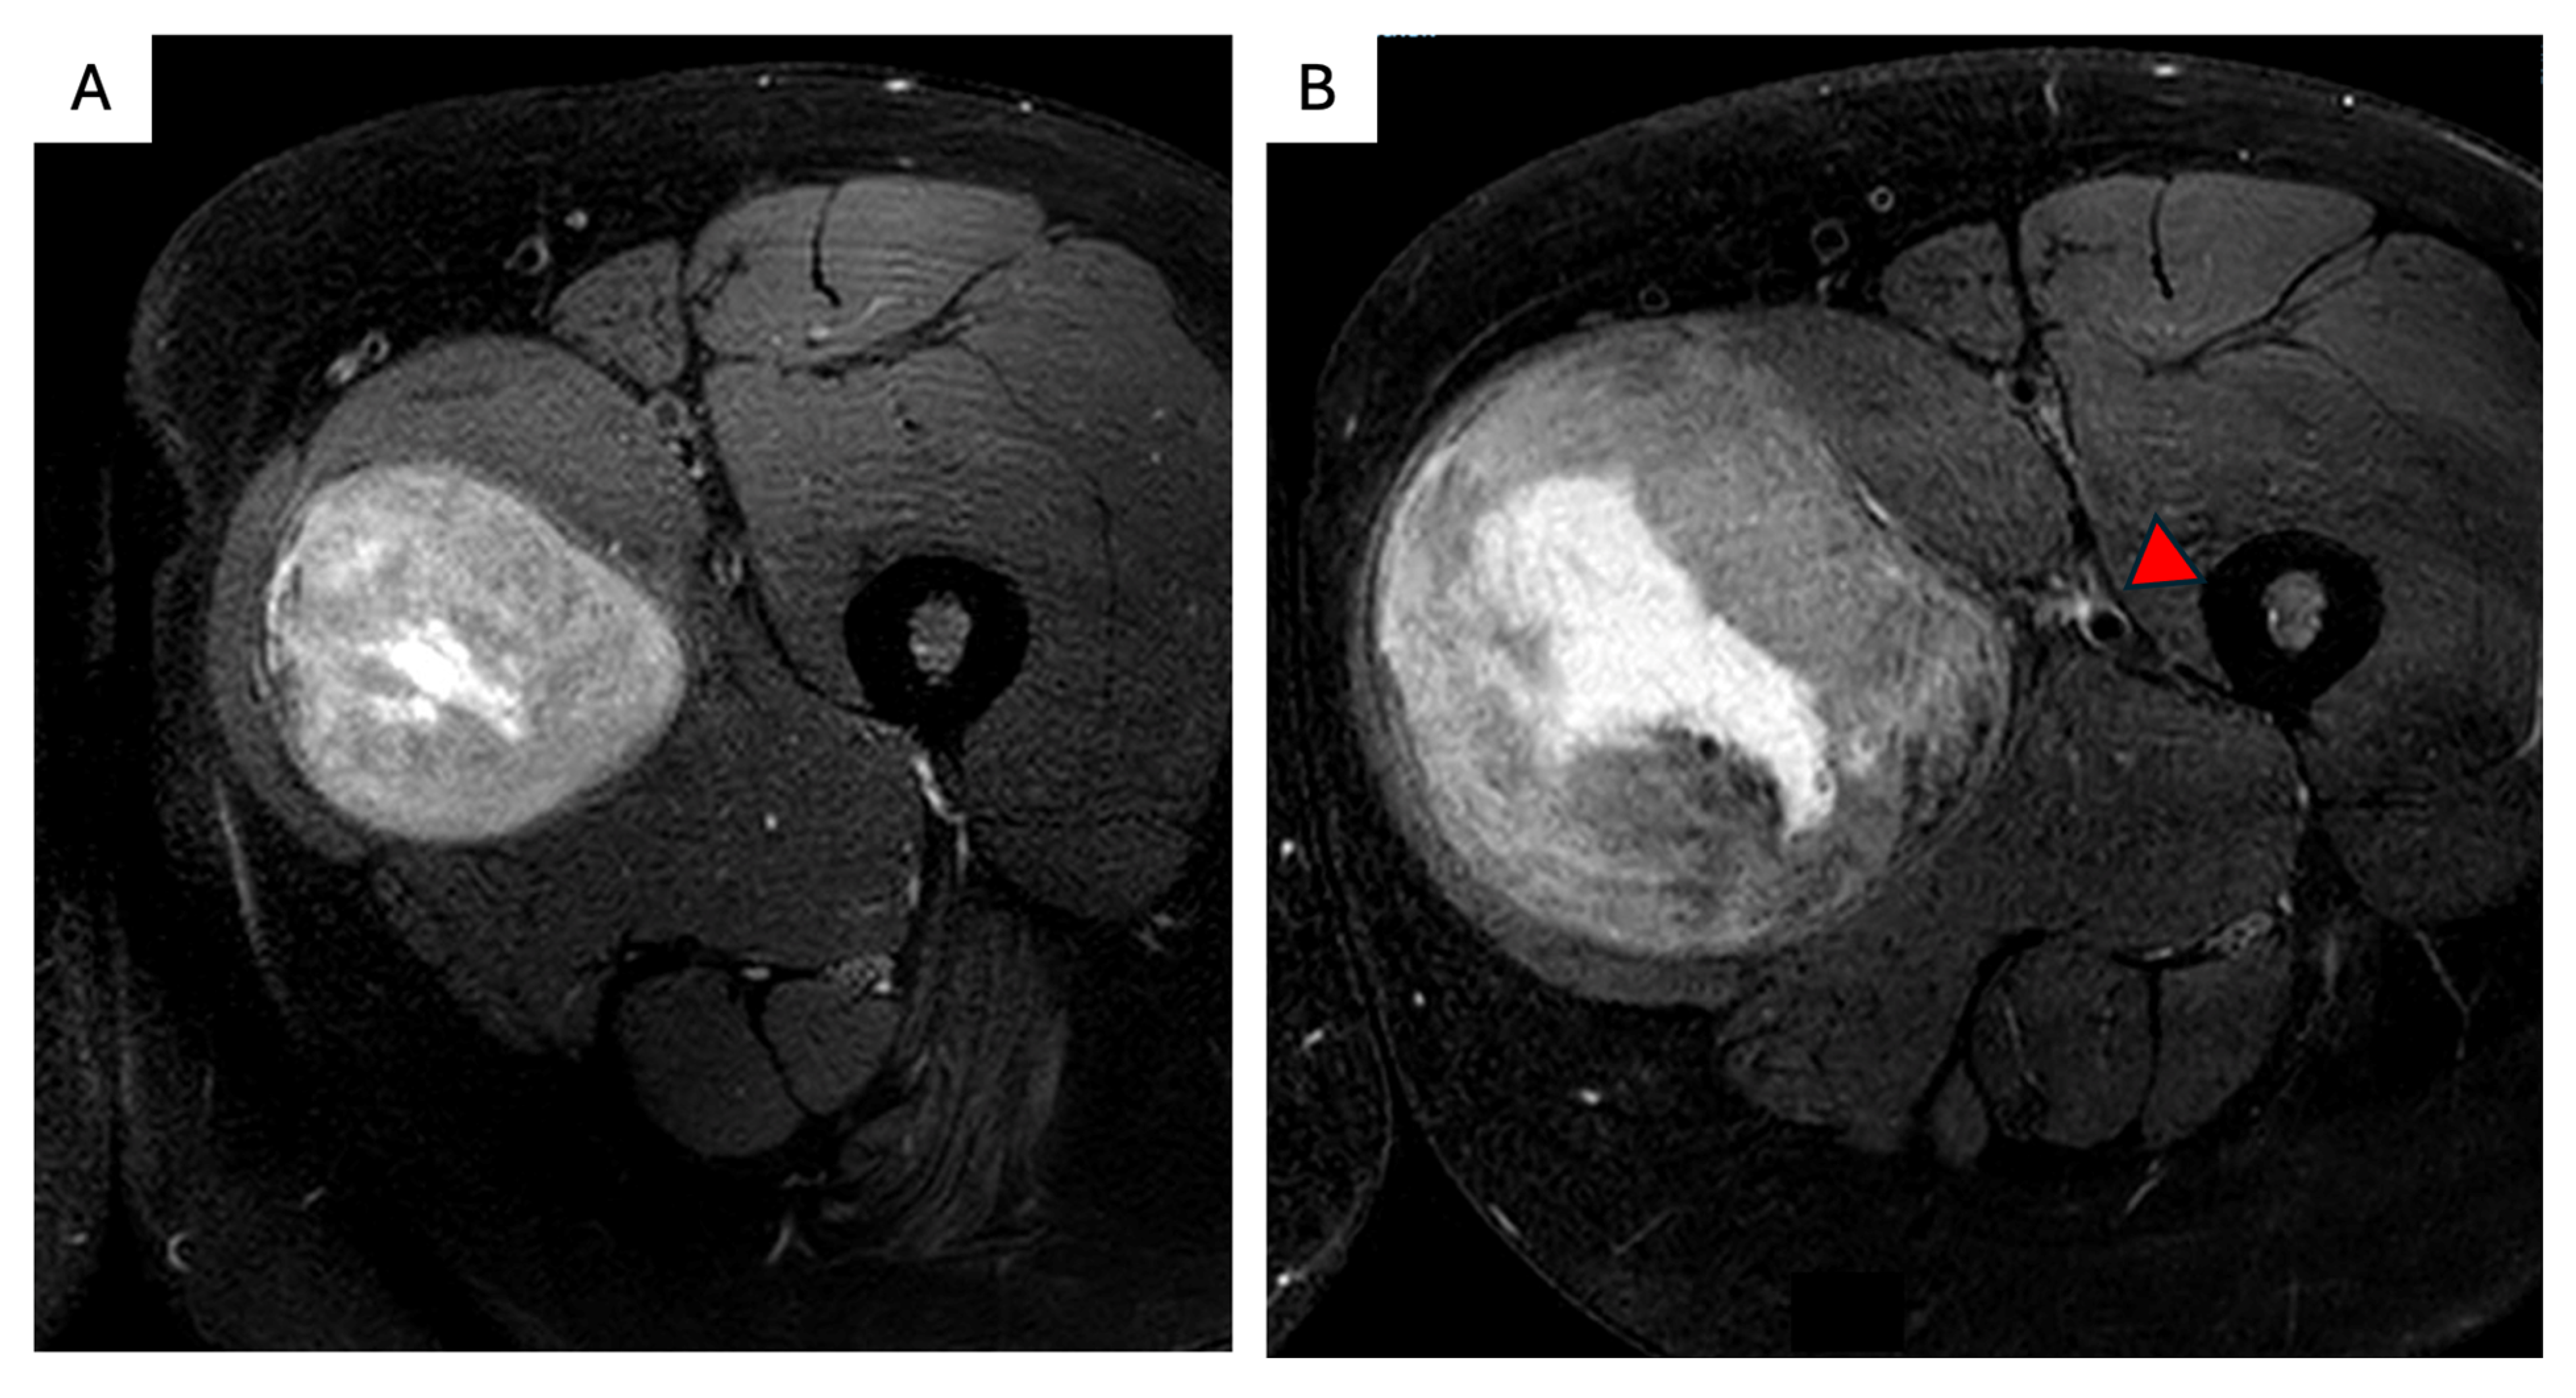

6. FAP-Associated Intraabdominal Desmoids

- Elective resection as primary treatment. In patients with resectable primary disease and low anticipated morbidity, complete macroscopic clearance can be achieved (Figure 3) with favorable operative outcomes in specialist centers [62]. When assessing resectability, key considerations include mesenteric vasculature involvement, anticipated length of small bowel and/or colonic resection, risk of short gut syndrome, and additional visceral involvement. The potential for future tumor growth and associated complications must also be carefully weighed [20,59]. In case of prior incomplete resection and evidence of residual disease, AS is recommended due to the possibility of an indolent course [63].